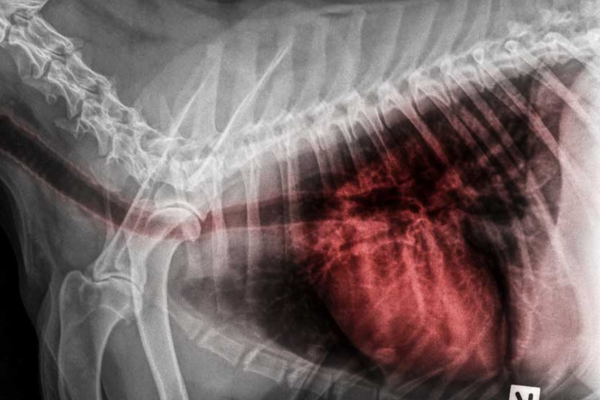

Khi cún có biểu hiện nôn trớ lặp lại, việc thăm khám thú y là cần thiết. Bác sĩ thường chỉ định chụp X-quang ngực và thực quản, đôi khi kết hợp chất cản quang để quan sát rõ đường đi của thức ăn.